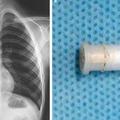

Deček pogoltnil piščalko in to je bilo slišati iz njegovih pljuč

Nenavadni primer "žvižgajočega kašlja."